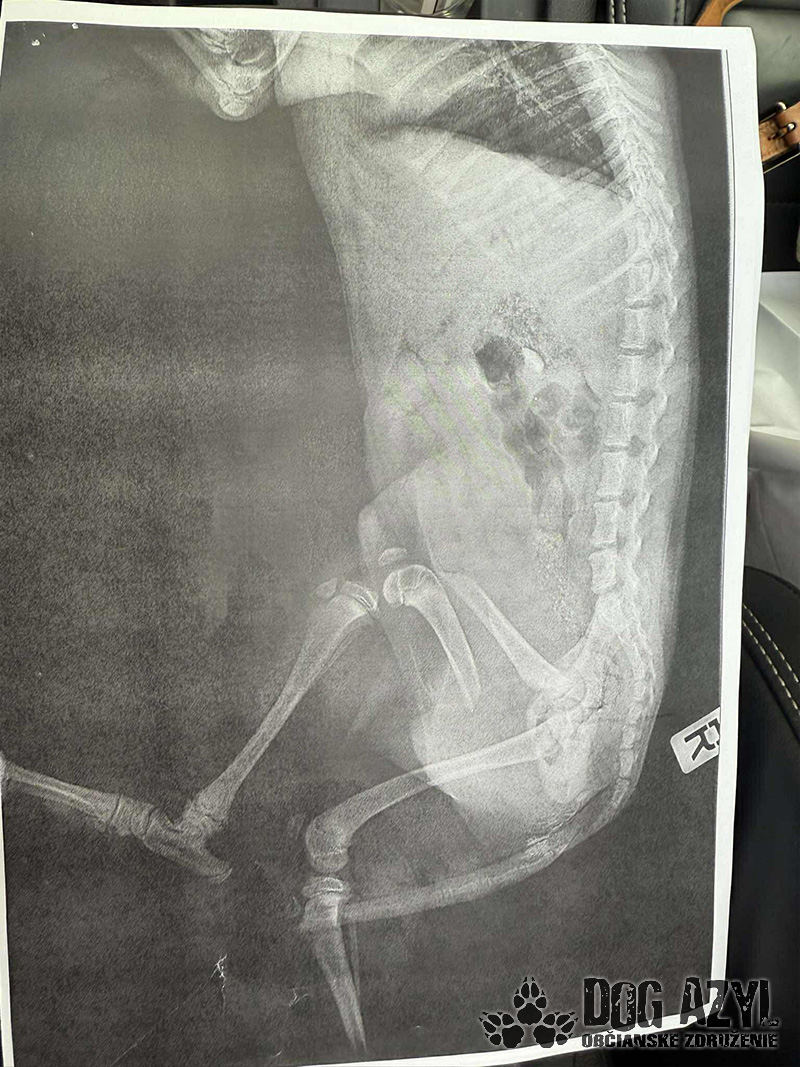

Drobec, ktorý medzičasom dostal meno Gerro, sa napriek všetkému celý čas tešil ľudskej pozornosti a krútil chvostíkom. Má veľmi škaredé zlomeniny prednej aj zadnej labky, pomliaždeniny na celom telíčku, ale našťastie lebka a chrbtica by mali byť v poriadku. Naše srdcia sú z tohto prípadu dolámané tiež na milión kusov, modlíme sa a veríme, že operácie zvládne! My budeme pri ňom a pomôžeme mu vo všetkom, v čom len bude treba.

Momentálne je hospitalizovaný u nášho veterinára, kde ho včera pripravovali na náročné operácie, ktoré by podľa plánov mal podstúpiť dnes. Čaká ho ešte veľmi dlhá cesta, ale pomôžeme mu zvládnuť každý jeden krôčik!